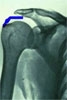

Normalny wygląd przyczepu mięśnia nadgrzebieniowego (m.supraspinatus), z lewej strony ścięgno mieśnia dwugłowego (m.biceps brachii), na dole głowa kości ramiennej. Na zdjeciu rentgenowskim na niebiesko.

Zerwanie całkowite przyczepu (X).